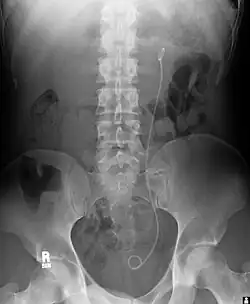

Ureteric stent

Example of a ureteral stent used to alleviate hydronephrosis of the kidney

Ureteral stents are used to ensure the patency of a ureter, which may be compromised, for example, by a kidney stone. This method is sometimes used as a temporary measure to prevent damage to a kidney caused by a kidney stone until a procedure to remove the stone can be performed.

An ureteral stent it is typically inserted using a cystoscope, and one or both ends of the stent may be coiled to prevent movement. Ureteral stents are used for various purposes, such as temporary measures to prevent damage to a blocked kidney until a stone removal procedure can be performed, providing drainage for compressed ureters caused by tumors, and preventing spasms and collapse of the ureter after trauma during procedures like stone removal. The thread attached to some stents may cause irritation but allows for easy removal by pulling gently.